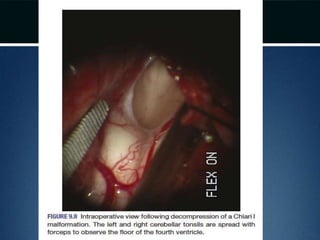

Posterior fossa decompression..

• Dura opened

• Arachnoid adhesions obstructing flow

removed and the floor of the 4th ventricle

examined

• Portion of occipital pericranium harvested

through a separate incision and duroplasty

performed